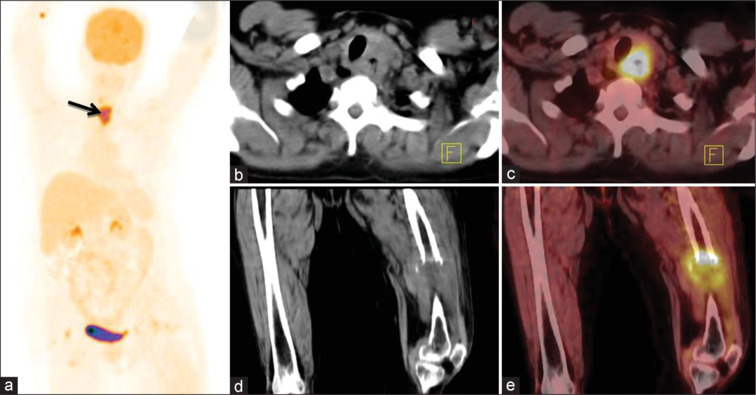

Results: Among total n = 74 (42 males and 32 females with mean age 59.4 ± 11.4; range 35-86 years) patients, SCC was seen in 78.4% and AC in 21.6% of patients. There is a progressively increased SUVmax value of primary tumor with nodal and distant metastases. 18F-FDG PET/CT showed disease of Stage I-II in 12.1%, Stage III in 20.2%, Stage IVA in 25.6%, and Stage IVB in 41.8% patients. There is agreement between 18F-FDG PET/CT and CECT chest and abdomen in the evaluation of regional lymph nodes (37.8% vs. 36.4%; κ - 0.96), nonregional lymph nodes (24.3% vs. 20.2%; κ -0.74), and distant organ involvement (21.6% vs. 17.5%; κ -0.82). In addition, 18F-FDG PET/CT found synchronous malignancies in 4.0% of patients.

Conclusion: 18F-FDG PET/CT metabolic parameters help in identifying metastatic involvement in morphologically equivocal and clinically suspicious lesions in carcinoma esophagus patients. Being a whole-body imaging modality, 18F-FDG PET/CT has inbuilt advantage to detect occult, distant metastases, and synchronous malignancies for effective staging and improving plan of clinical management.